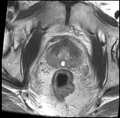

• Testing on 10 clinical datasets was performed using BRAINS+ITK4

• registration was successful in 8 out of 10 cases, based on visual inspection; further investigation is needed for the failed cases and larger scale validation